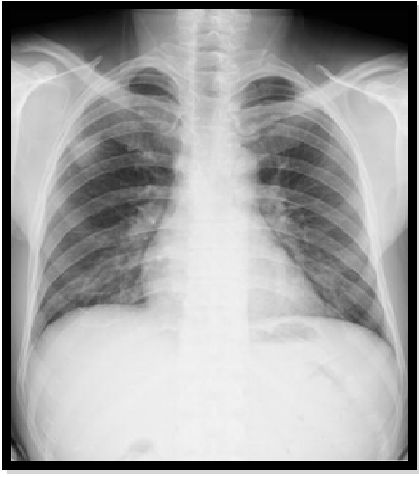

胸部X光片和CT扫描显示(图:1,2,3,4,5,6,7):

1、肺部空腔,包含坚实的圆形物质,通过空气边缘与墙壁分开。此功能称为“空气新月”标志。

2、另一个常见特征是腔壁和邻近胸膜增厚。

3、这种真菌球可能是移动的。

图6:胸片显示右上叶阴影,被空气新月包围:腔内的真菌球。